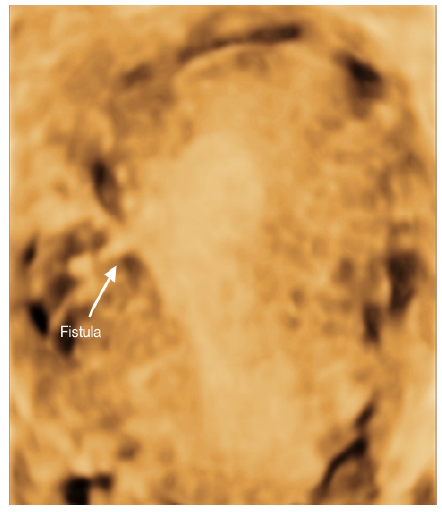

Misdiagnosis of Intra-Uterine Fistula as Hydrosalpinx Post Embolization for a Uterine Myoma: What Went Wrong?

Teddy Tadros, Laura Melado, Jonalyn Edades, Barbara Lawrenz, Francesco Ruiz and Human Fatemi. 12(6): 01-04.